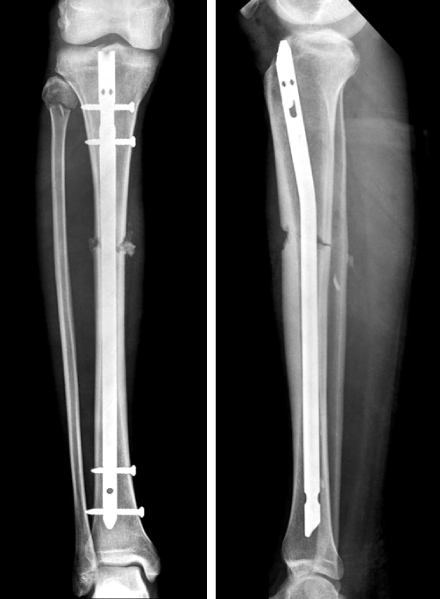

Fig. 8

(A, B) Initial radiographs show the proximal tibial fracture at the proximal meta-diaphyseal junction.

(C, D) Postoperative radiographs show good alignment of the fracture fixed with a locked tibial nail and blocking screws to prevent malalignment. A blocking screw was placed lateral to the central axis to prevent valgus angulation and the other blocking screw was placed posterior to the central axis to prevent apex anterior angulation.

Fig. 8 (A, B) Initial radiographs show the proximal tibial fracture at the proximal meta-diaphyseal junction. (C, D) Postoperative radiographs show good alignment of the fracture fixed with a locked tibial nail and blocking screws to prevent malalignment. A blocking screw was placed lateral to the central axis to prevent valgus angulation and the other blocking screw was placed posterior to the central axis to prevent apex anterior angulation.